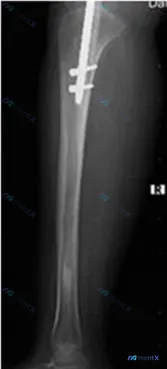

整理了一个很有启发性的胫骨骨折术后影像读片思路,不是直接给答案,而是把「看到片子后怎么一步步思考」的逻辑写出来,大家可以一起讨论。 --- 先看「核心影像事实」 这是一张右侧胫骨正位(含膝关节)X光片(结合描述的完整影像评估): 1. 内固定状态: 胫骨髓腔内有一枚金属髓内钉,近端有2枚横向锁钉,位...